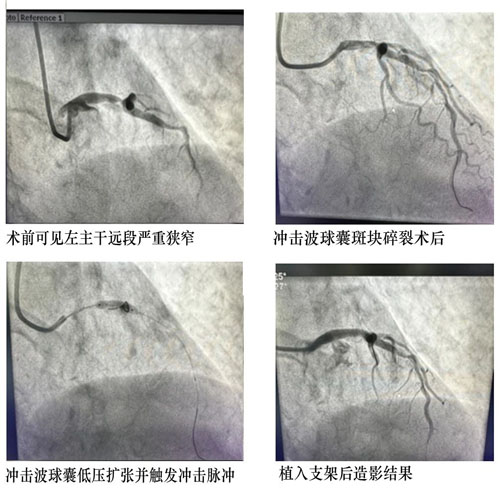

近日,我院心血管內(nèi)科獨(dú)立完成本地區(qū)首例冠脈血管內(nèi)沖擊波球囊斑塊碎裂術(shù)。

患者,男,80歲,1個(gè)月前因胸痛收住院。冠脈造影提示左主干至前降支鈣化病變導(dǎo)致80-90%狹窄,右冠脈閉塞。患者冠脈病變嚴(yán)重,手術(shù)風(fēng)險(xiǎn)較高,先期開通閉塞右冠病變并植入支架治療,此次處理左主干病變。

患者年齡大,左主干重度狹窄并嚴(yán)重鈣化,常規(guī)PTCA(經(jīng)皮冠狀動(dòng)脈腔內(nèi)血管成形術(shù))難以充分處理病變,可能導(dǎo)致支架無法順利通過、膨脹不全等風(fēng)險(xiǎn)。心血管內(nèi)科CCU討論后決定應(yīng)用沖擊波球囊,選擇3.5×12mm Shockwave球囊精確定位于LM-LAD鈣化病變嚴(yán)重處,根據(jù)標(biāo)準(zhǔn)操作流程,4ATM低壓力擴(kuò)張球囊,累計(jì)觸發(fā)2個(gè)周期的沖擊波鈣化斑塊碎裂術(shù),利用聲波壓力震碎血管壁內(nèi)鈣化沉積,解決了嚴(yán)重鈣化病變普通球囊無法充分?jǐn)U張的難題,復(fù)查冠脈造影見鈣化病變狹窄明顯減輕。經(jīng)1小時(shí)手術(shù)治療,成功植入藥物支架1枚,解除血管狹窄,患者未再有癥狀,順利出院。